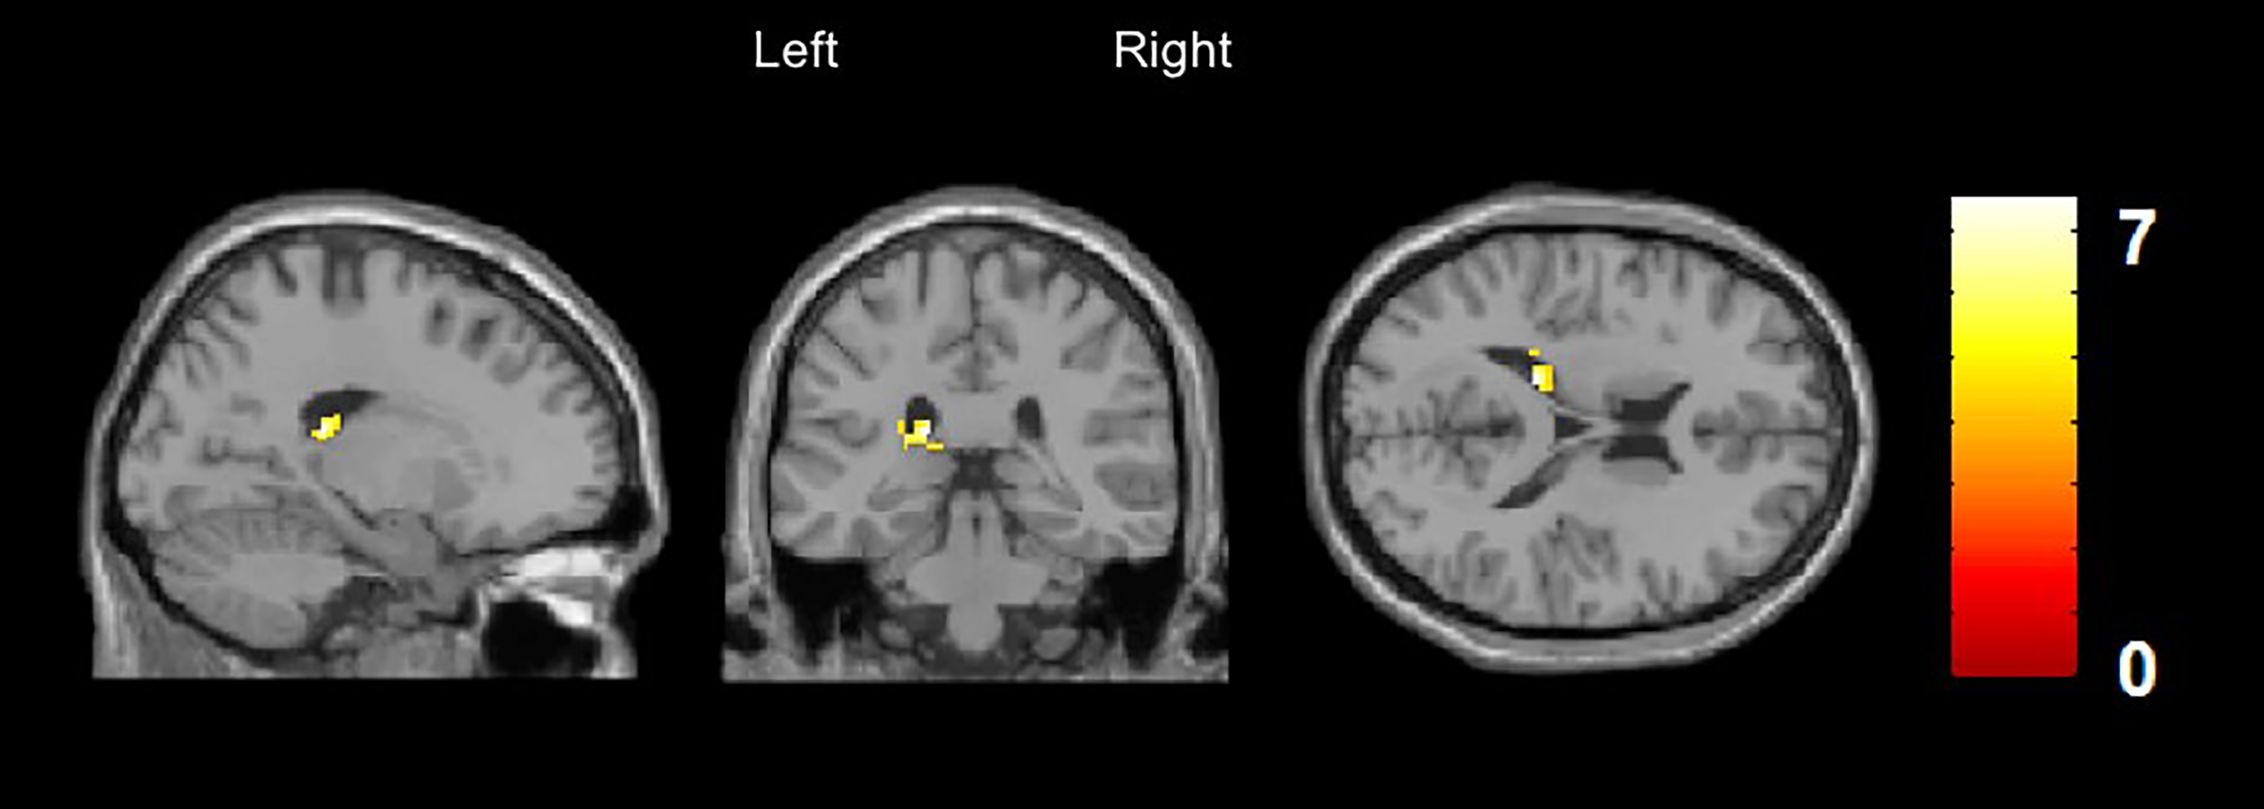

A significantly increased rCBF was discovered in the left caudate nucleus (x/y/z = −18/−32/18, t = 7.6, cluster size = 95) and in the left inferior temporal gyrus (x/y/z = −60/−44/−20, t = 6.7, cluster size = 87) in patients with DP/DR disorder compared to healthy controls. The increase of rCBF in the left caudate nucleus survived FWE (p < 0.05) and small volume correction for the region of interest (Figure 2).

Figure 2

Arterial Spin Labeling Analysis for gray matter regional cerebral blood flow (rCBF), whole brain, T-contrast in DP/DR disorder patients (n = 6) vs. healthy controls (n = 6), uncorrected at p < 0.001 (x/y/z = −60/−44/−20, t = 6.7). Yellow areas indicate significantly increased CBF in the left caudate nucleus in DP/DR as compared to controls.